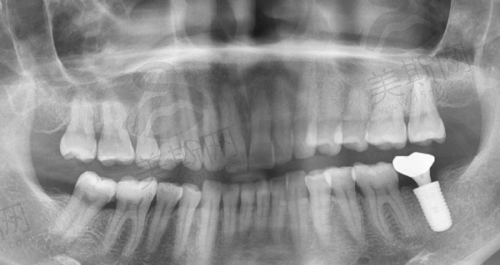

深圳穗华口腔医院在应急处理方面具有专精的实力。医院拥有精良的设备和技术,能够为患者提供精细的诊断和有效的治疗。例如,在数字化种植技术方面,采用德国ICX导航种植系统,术前3D模拟误差≤0.1mm,能有效避免损伤神经血管。即使是在急诊情况下,对于需要种植牙齿的患者,也能提供安心、精细的手术。

医院的医生团队实力雄厚,学科带头人李芬有二十多年临床经验,可开展高难度种植牙和半/全口种植,成功几率高。种植医生王秀珍可开展微创种植牙、残根拔除、半/全口牙颌种植等。在遇到口腔急诊时,这些经验多的医生能够快速做出正确的判断,并制定出合适的治疗方案。

深圳穗华口腔医院急诊的费用是特别多患者关心的问题。在种植牙价格方面,官网公示种植牙全包价,如韩国登腾3980元/颗,含CT检查、即刻修复 。但不同种植体品牌、患者口腔具体情况及治疗方案会导致价格有所差异。